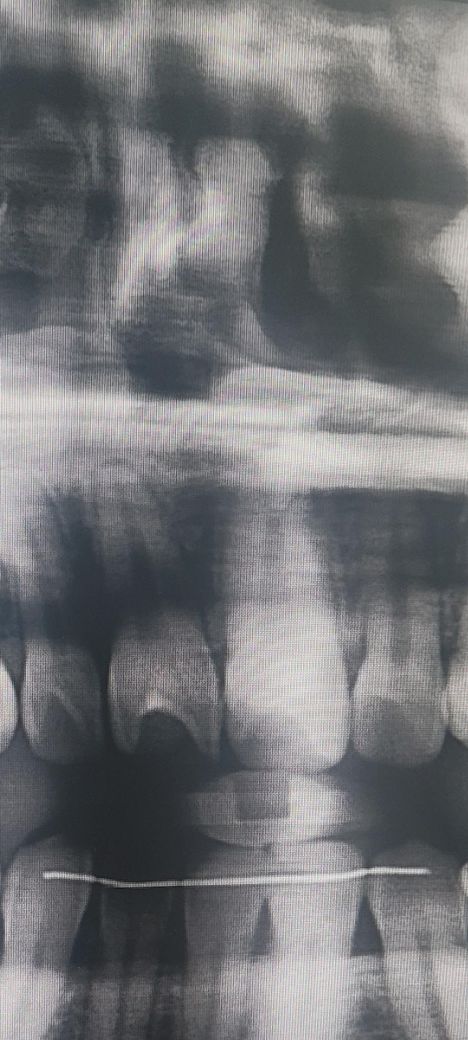

앞니가 흔들리는거 같아요 엑스레이 좀 봐주세요

상악 앞니가 흔들리는거 같아서 8월에 치과에서 엑스레이를 찍어봤습니다. 그때 의사선생님께서 별 이상 없다고 하셨는데 얼마전 물로 여러번 격정적이게 가글을 했는데 그 이후로 좀 이상해요.

2개월 전 엑스레이인데 제 상악 앞니들이 뿌리가 짧다거나 잇몸뼈가 없다거나 그런 문제가 있는지 봐주실 수 있을까요?

음 오른쪽 위에 측절치의 경우에는 치주인대가 늘어나있는 것처럼 보이긴 합니다. 치아에 과도한님이 지속적으로 가해졌을 경우 해당 증상이 생길 수 있기 때문에 자세한 확인을 위해서 그래서 치과에서 진료를 받아보는 것이 좋습니다.

엑스레이 상으로는 크게 문제가 없어 보입니다. 아마 교합이 안좋아서 그럴수도 잇으니 교합체크를 한번 받아보세요.

사진상에서는 특별히 문제는 모르겠습니다. 흔들리는것이 맞다면 다시 치과 가보시는 게 좋겠습니다.

특별히 엑스레이상 이상소견은 없는 것 같습니다 보다 자세히 체크하기 위해서는 큰 사진 말고 작은 치근단 엑스레이를 찍어봐야 합니다